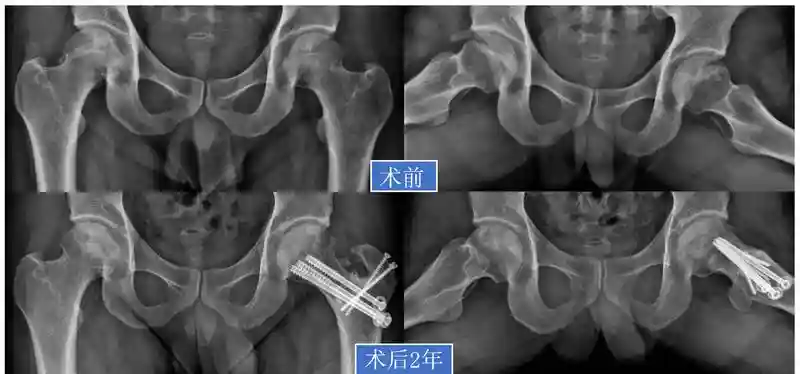

36岁的庄先生长期受皮肤湿疹困扰,每次发作时他就涂药膏或吃口服药,没想到这些药里含有激素,不知不觉中就“伤”了骨头,出现双侧股骨头坏死。

陈镇秋教授为他进行详细检查后,制定的方案是——右侧髋关节保守治疗,左侧采用手术保髋。在分离股骨头血管软组织瓣后,通过股骨颈截断旋转,把没有发生坏死的部分起“支撑”作用,也就是负重区为正常骨质,而坏死的部分不在负重位,给发生坏死的股骨头部分进行“减负”休息,可加速修复。

术后2年随访,庄先生双侧坏死区域修复稳定,双髋无疼痛,功能良好。